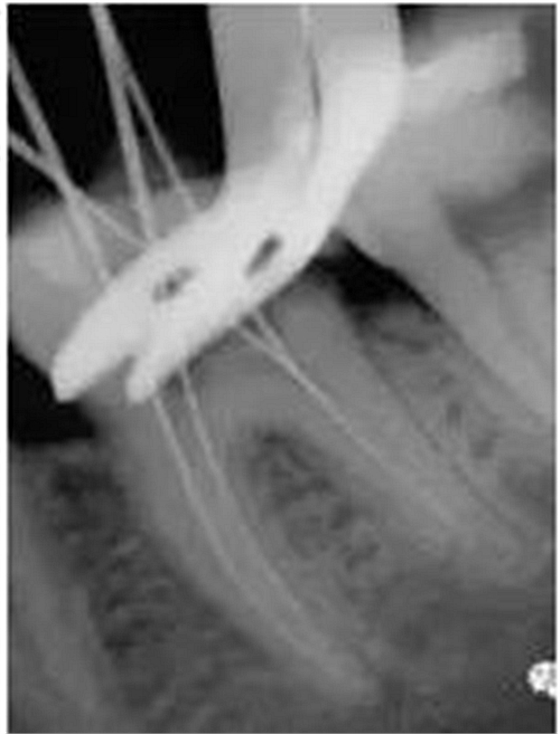

3、根管口的直線通道:特別對于彎曲根管!預備根管之前是否重視這個環(huán)節(jié),盡管找到了根管口,銼也能順利進入根管,但根管口的直線通道是否建立也是衡量醫(yī)生操作技能的重要依據(jù)。

方法很多:手動器械操作時我們可以采用價格便宜的“GG”鉆,PROTAPER機動預備時可以采用SX銼。

圖7彎曲根管冠部處理之前 圖8用GG鉆或SX銼進行預備

圖9處理后形成的直線通道

8、彎曲根管最好采用不銹鋼銼同鎳鈦銼配合使用:用不銹鋼器械預備彎曲根管中下段,鎳鈦器械預備中上段!